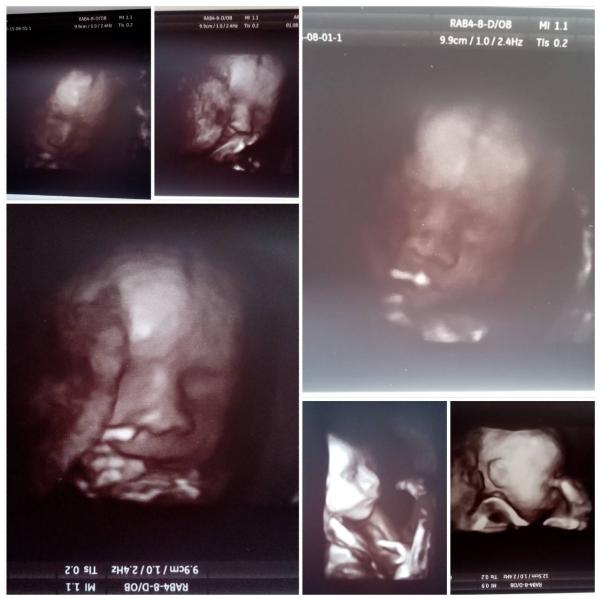

девчулечки-красотулечки 💚знакомьтесь с Ангелиной Александровной 💎Боже,какое же это счастье 💗💗💗моя сладкая 🍰моя ягодка 🍓это подарок от Бога 👼этот ангелок вытягивала свои ножки😍я жевала жвачку,а эта принцесса чмокала свою сладкую ручку 😍💙💋прекрывалась ручками,ножками 😄отвечала пинками на движение врача 😄😍Врач сказала,что щеки точно мамины 😂😂😂💓поскорее бы родить, взять ее на ручки 😘Врач потрясающая,все расказала,все показала 😍вес 689 грамм,рост 33 см 😍😘поговорили,и решили что видео нам не надо,Врач...

Хотела поделиться радостью,вчера ходила на третье УЗИ (делала в диалайне в красноармейском р-не врач Кин Ирина Александровна) .

Все у нас хорошо,маловодье не подтвердилось ,вес на два дня опережает сроки(1820) ,лежим головкой вниз😍,на шее есть пуповина,но это не обязательно обвитие,возможно так лежит пуповина.

Но больше всего меня обрадовало то,что нам сказали пол 😃 у нас будет ПРИНЦЕССА!!!👸🏼👼🏼

От врача я просто в восторге,все показала,личико я прям отчетливо видела(она такая красавица😭😱),так же п...